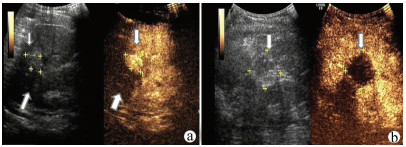

肝病超声诊断指南

中华医学会超声医学分会, 中国研究型医院学会肿瘤介入专业委员会, 国家卫生和健康委员会能力建设和继续教育中心超声医学专家委员会

2021, 37(8): 1770-1785. DOI: 10.3969/j.issn.1001-5256.2021.08.007

超声检查无创、实时、价廉,无辐射、便于反复进行,是最常用的肝脏影像学检查方法。近年来,超声检查新技术如超声造影、弹性成像发展迅速,可有效鉴别肝内占位性病变性质、评估肝纤维化和门静脉高压程度以及监测肝病治疗效果,在临床肝病及其介入治疗中发挥重要诊断价值。本指南规范了肝病多模态超声技术(灰阶超声、彩色多普勒超声、超声造影、弹性超声)检查的仪器调置、患者准备及医生检查方法;对肝脏弥漫性病变(炎性病变、纤维化、硬化)、多种占位性病变及肝病介入操作的多模态超声技术诊断标准进行了定义和规范,同时推荐了超声监测周期及肝脏疾病超声诊断报告书写规范。